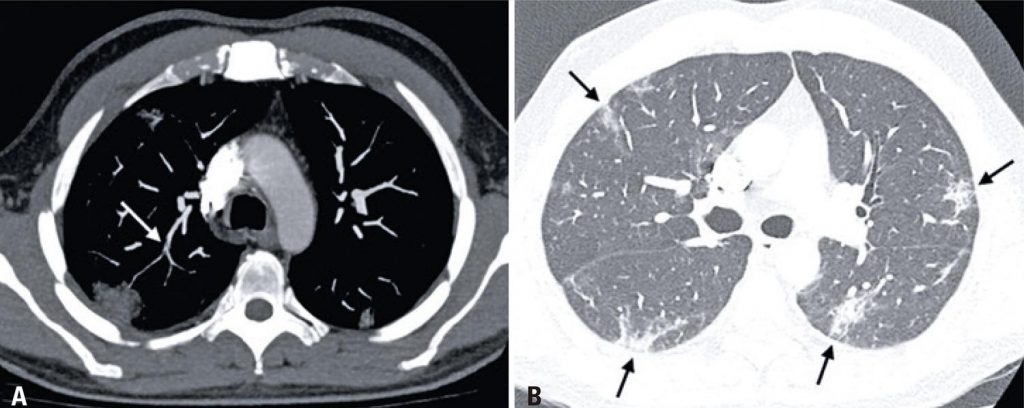

Motivo de grande preocupação no cenário global atual, a pandemia pelo novo coronavírus (COVID-19) tem sido um dos grandes motivos da realização de tomografias computadorizadas de tórax, seja na avaliação inicial ou no controle evolutivo. Esses pacientes apresentam aumento do dímero D, achado provavelmente relacionado a um estado de hipercoagulabilidade e que marca pior prognóstico.( )A seguir, ilustramos dois casos de pacientes com confirmação laboratorial de infecção pelo coronavírus e sinais de tromboembolismo pulmonar (TEP) – associação já descrita.( , )

Paciente do sexo masculino, 49 anos, encaminhado para angiotomografia do tórax devido à piora da dispneia, surgimento de dor torácica e elevação do dímero D (711ng/dL) no sétimo dia de internação. Evidenciou-se falha de enchimento em ramo arterial segmentar do lobo superior direito, compatível com TEP ( ), bem como alterações típicas para a pneumonia pelo coronavírus ( ).( , )